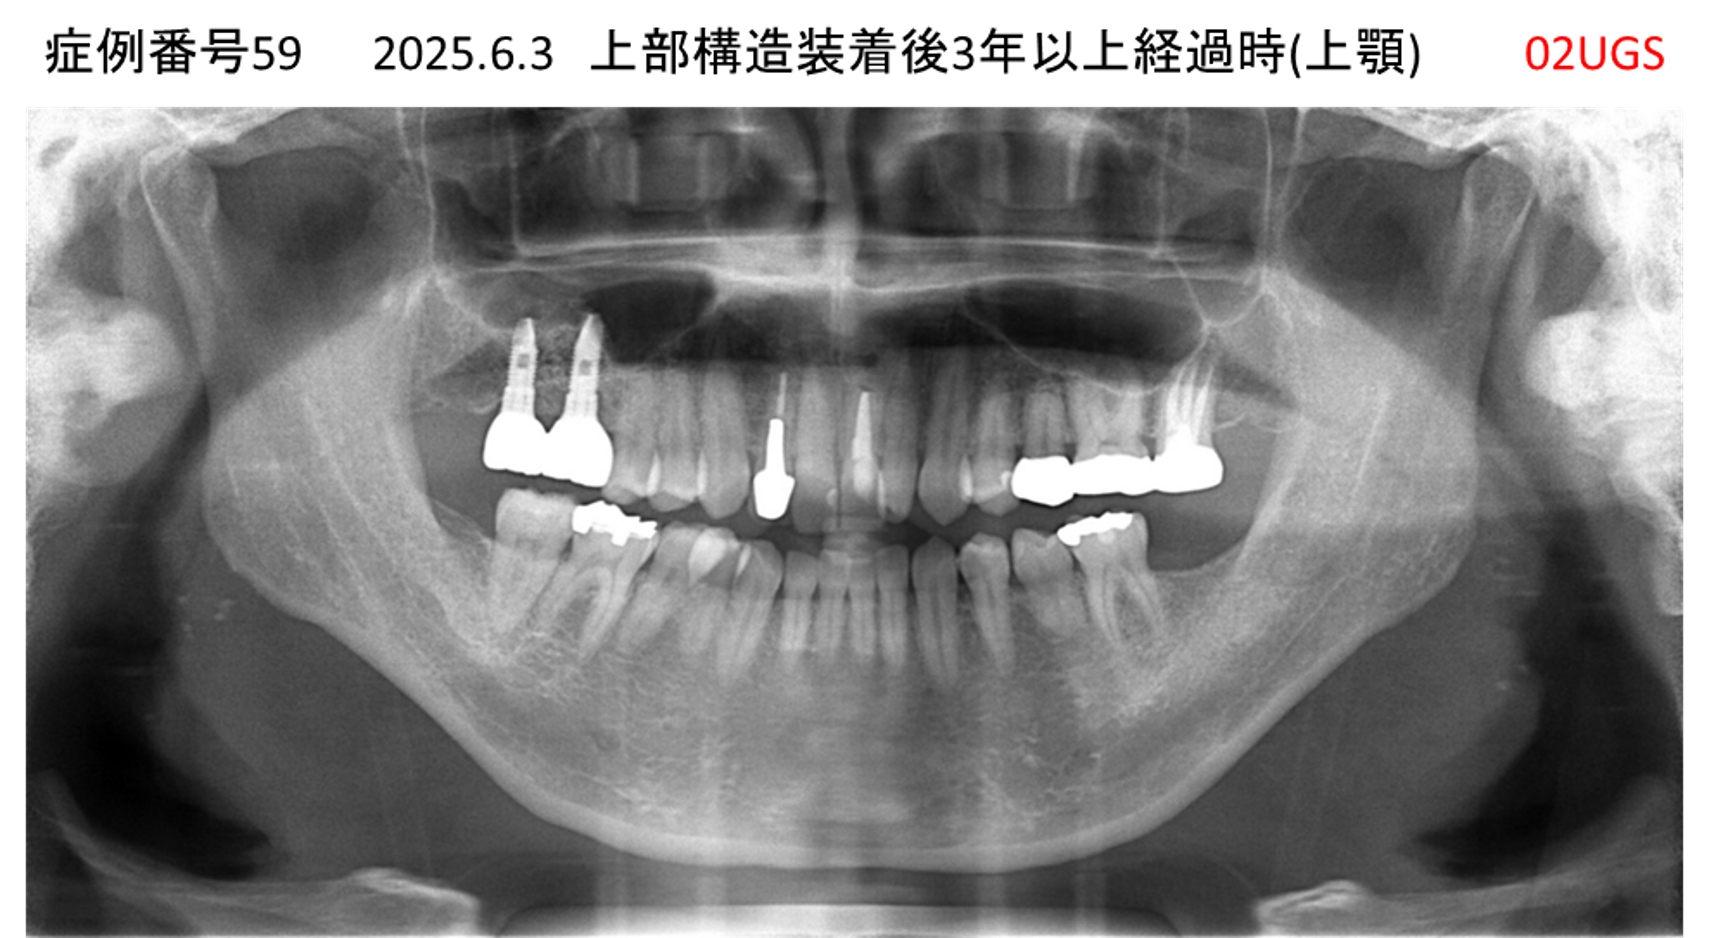

全く噛めない患者様のインプラント症例

| 治療名称 |

インプラントAGC |

| 治療費用 |

860万円+税 |

| 治療期間 |

12か月 |

| 患者さんの症状(主訴) |

全く噛めない、ごはんが後もに食べられるようになりたい、人前で口元を隠したくない |

| 治療内容 |

サイナスリフト、GBR、インプラント、AGC |

| 治療結果 |

しっかり噛めて踏ん張ることができる。食べ物をを選ばなくて済む、何でも食べられる、体重が増えた。見栄えがきれいすぎて自分じゃないみたい |

| 治療の注意点(リスク/副作用) |

インプラントが壊れたら再治療が必要 |